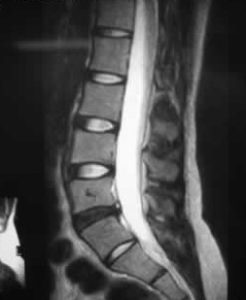

醫生會透過了解病史、檢查肌肉及神經反射狀況來尋找致病原因,也會讓病人做些引起疼痛的動作供醫生作判斷,若有需要也會要求患者做磁力共振掃描(MRI),以檢查椎間盤突出有否牽涉周邊脊椎神經線受壓。亦可從磁力共振掃描看見椎間盤失去水份及膠原蛋白而變黑,這就是退化性椎間盤的變化。

從磁力共振掃描看見椎間盤會因為失去水份及膠原蛋白而變黑,這就是退化性椎間盤的變化。